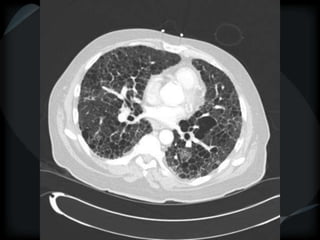

Septal Pattern – lymphatic/venous

● Smooth – pulmonary veno-occlusive disease, mitral

stenosis, capillary hemangiomatosis, LC

● Beaded – lymphangitic carcinomatosis, lymphoma,

lymphangiomatosis, sarcoid

beaded

PHTN – PA 39mm

39.2mm

PHTN and septal thickening

? PVOD